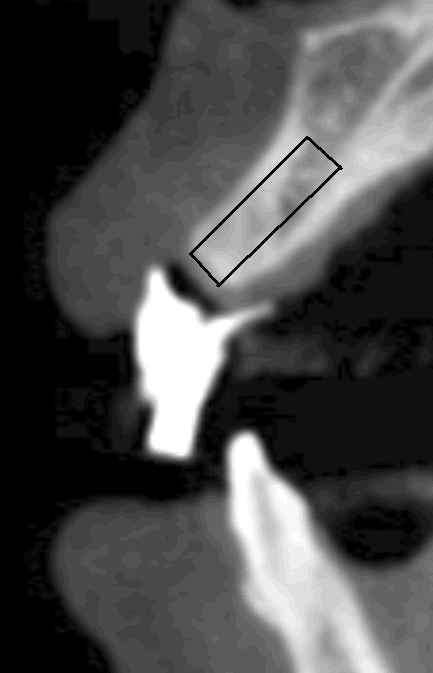

The originally designed long axes of implants at the tooth #7 (Fig.6) and #8 (Fig.7) are determined by wax-up, but they are not aligned well with the long axis of the alveolar ridge. In fact, the long axis of the natural tooth (#9 in Fig.8) is also not coincided with that of the ridge. That is, the root of the right central incisor is not inserted in the middle of the ridge. This orientation is good from the prosthetic point of view, but we cannot place the largest and longest implant, or fenestration is most likely to happen labially. An oral surgeon would like to place an implant (black box) along the long axis of the ridge (Fig.7'). Back to main text